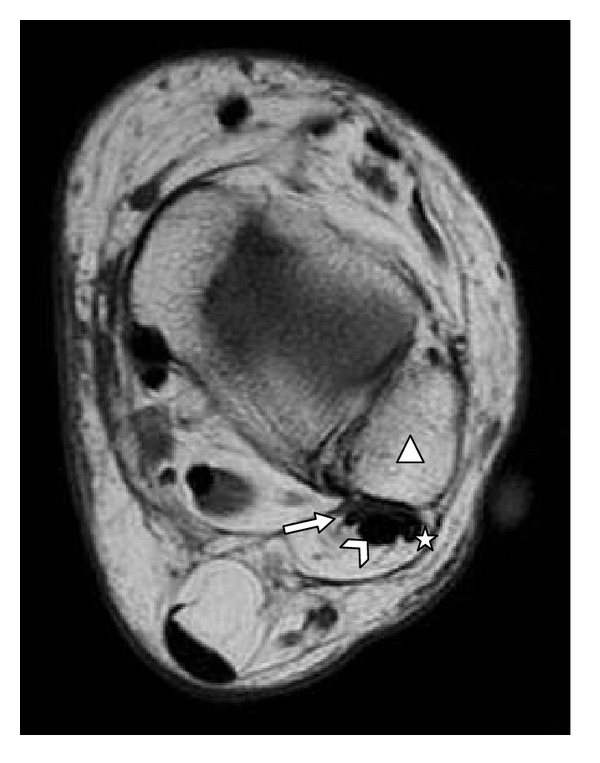

Objective. Quantify the presence of the fibularis quartus muscle and correlate it with the individual's sex and concomitant presence of the fibularis tertius muscle. Materials and Methods. We evaluated 211 magnetic resonance examinations (43.13% men and 56.87% women) on the ankle and hindfoot, produced between 2009 and 2011. Results. The fourth fibularis muscle was found to be present in 7.62% of the examinations and 75% of these also contained the fibularis tertius muscle. Conclusion. The incidence of the fourth fibularis muscle is variable; moreover, its incidence does not depend on the individual's gender or the presence of the fibularis tertius muscle.